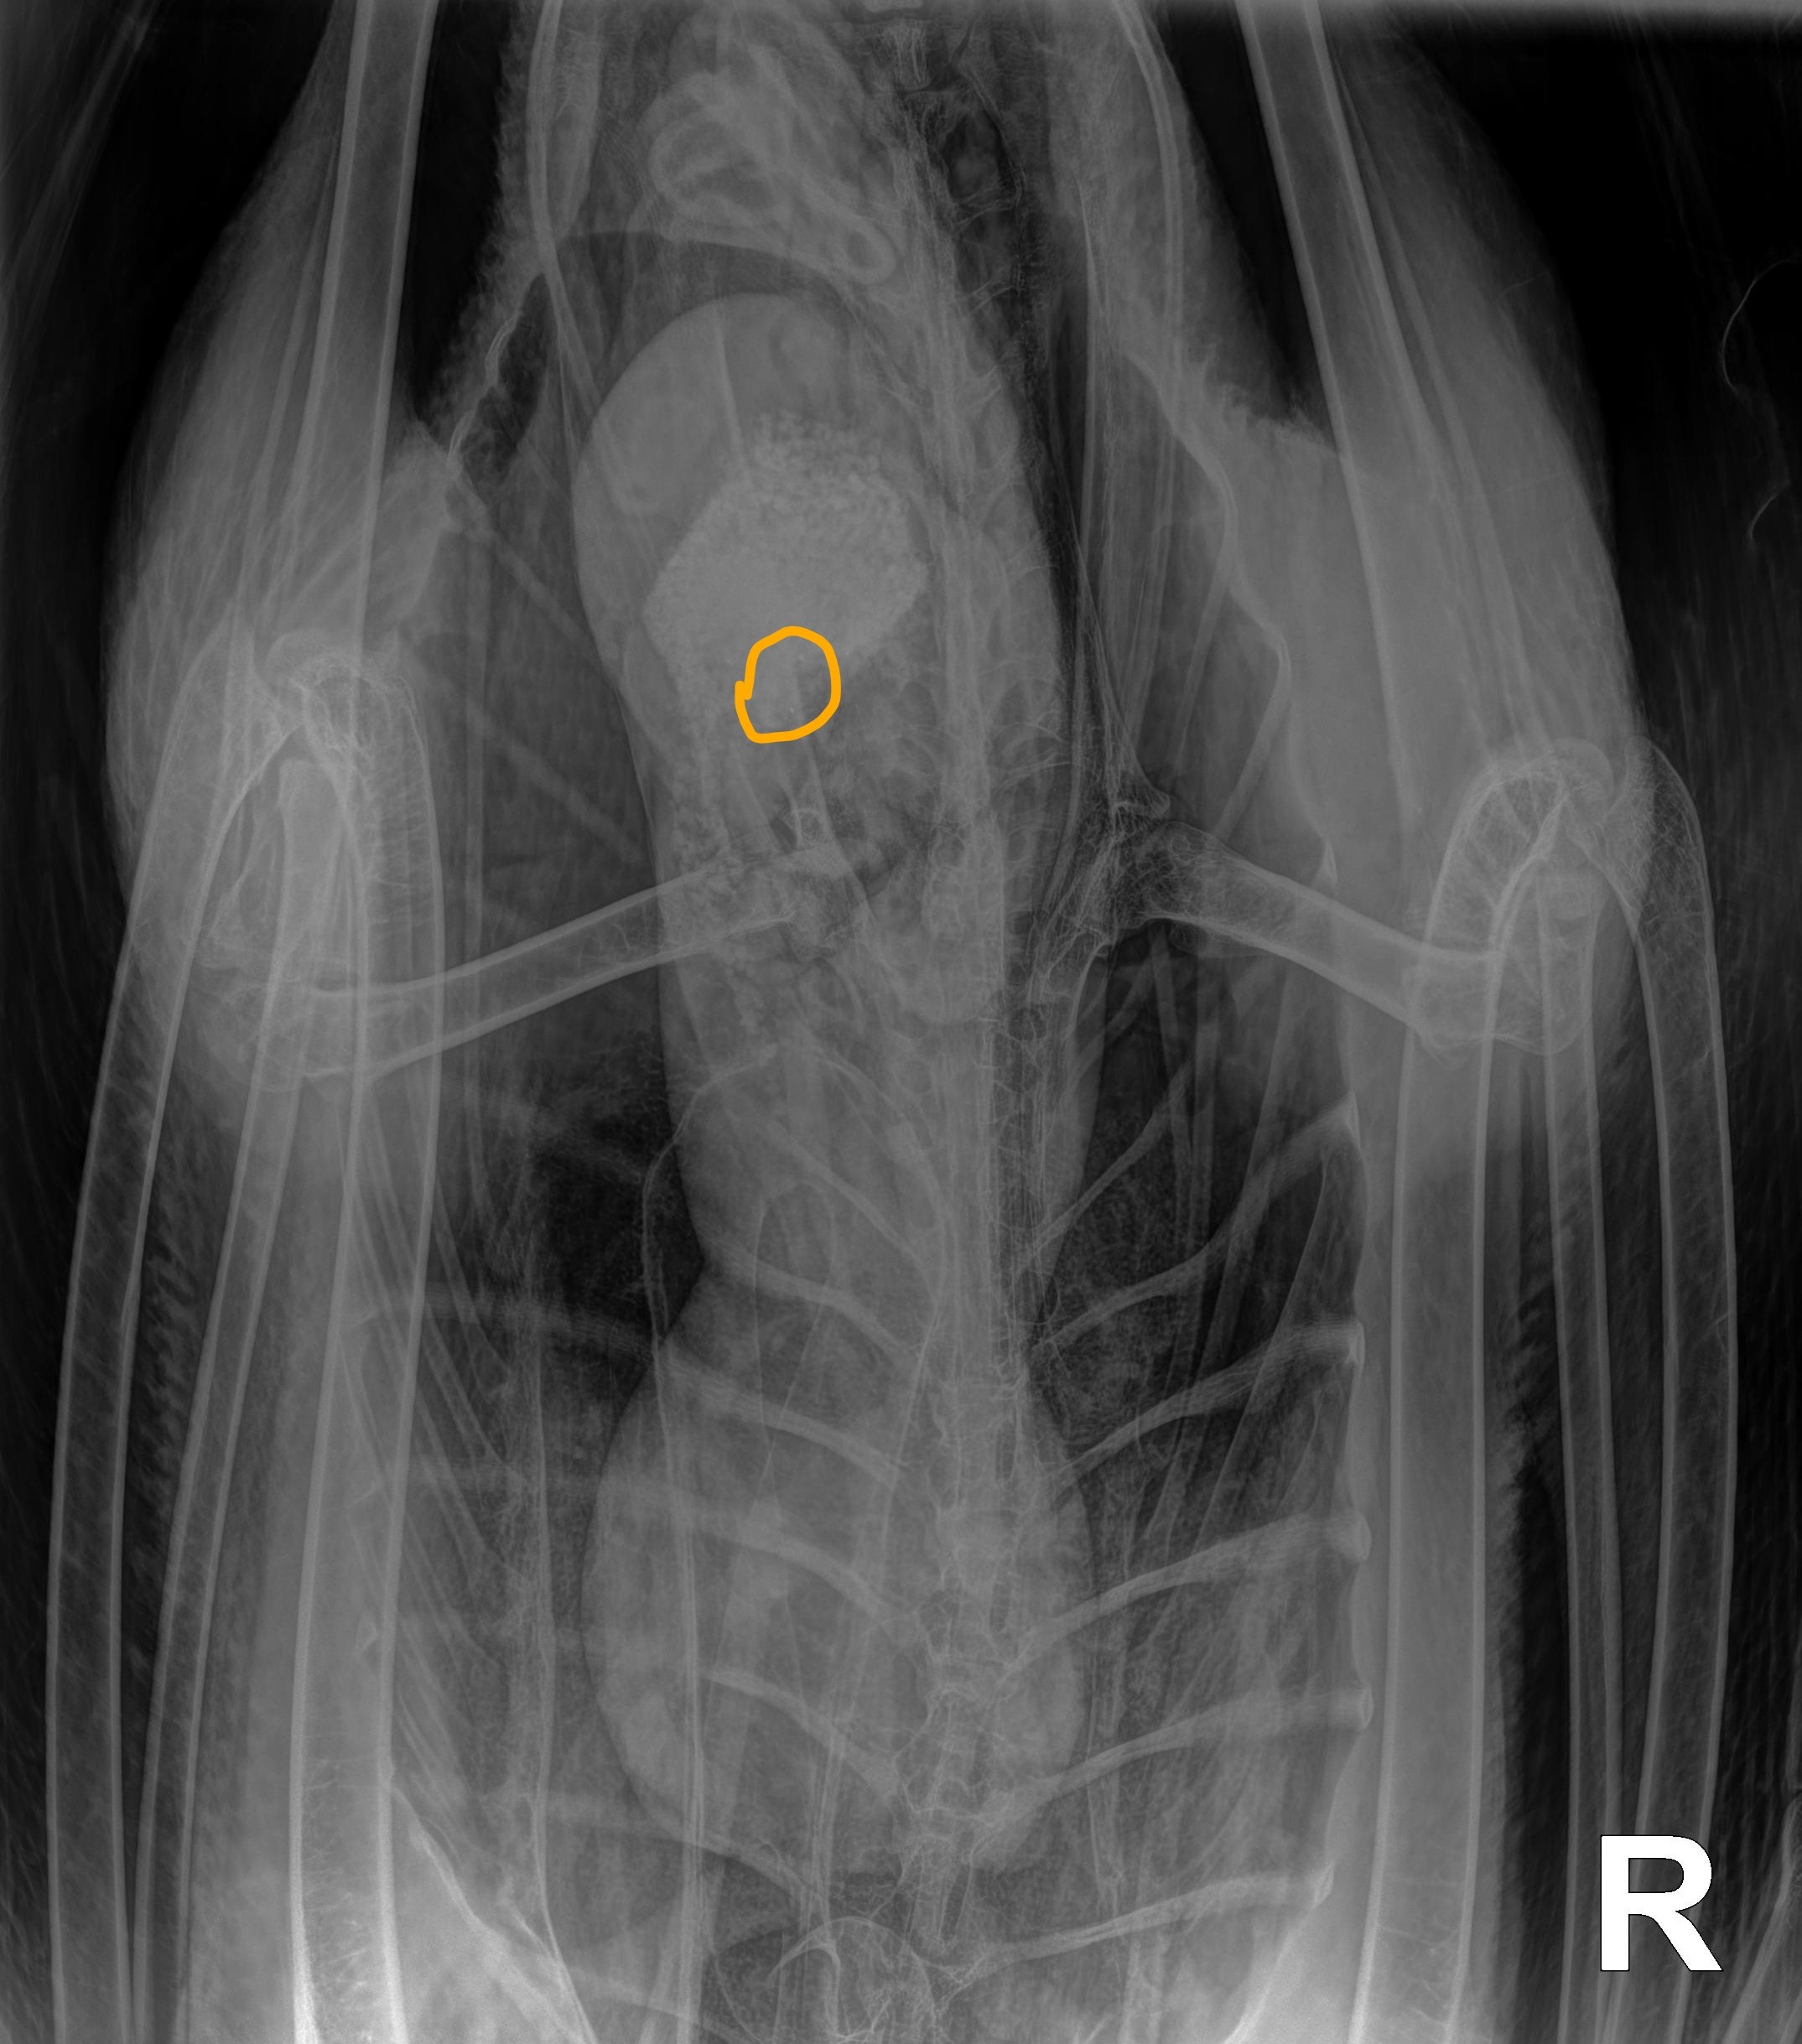

During the past 45 days, several x-rays have been taken to determine the status of the lead in the digestive tract as well as several blood lead level tests to monitor lead levels.

Today we’re happy to report the blood lead level was down to 21.9. There’s still a way to go, but finally what feels like progress.